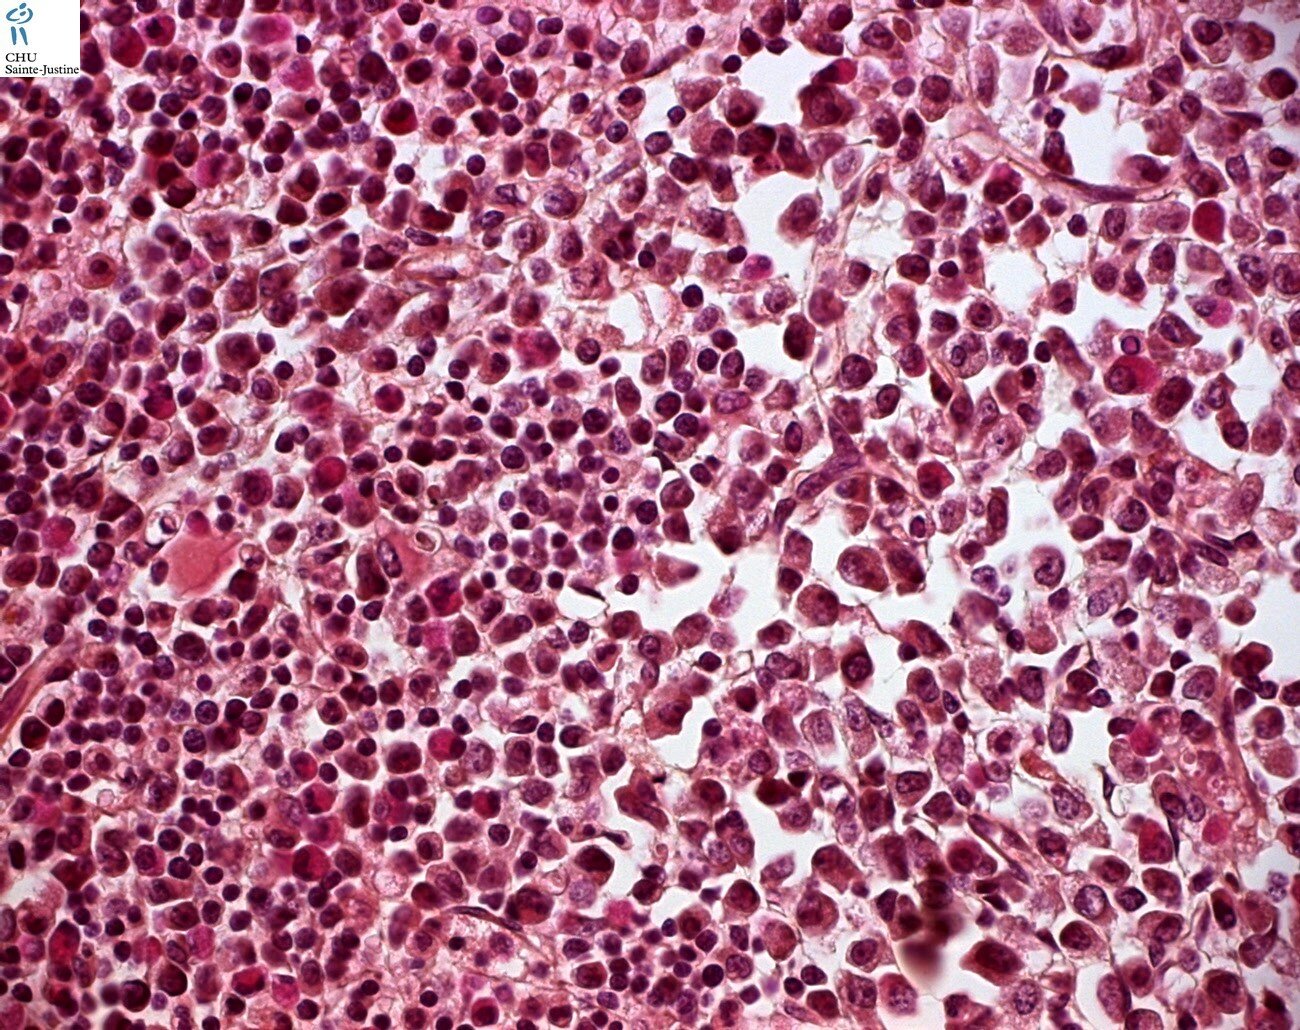

Morphology